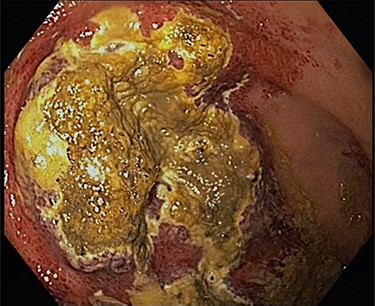

The decision was made to perform an upper GI endoscopy to evaluate the mucosa before potential surgery. Endoscopy revealed generalized mucosal erythema with intramucosal bleeding in the gastric fundus and corpus along the greater curvature of the stomach. Additionally, two massive areas of necrosis, measuring three and six centimeters in diameter, respectively, were found on the margin between fundus and body (Fig. 2).

Shown is a large necrotic area in the gastric fundus and corpus along the greater curvature